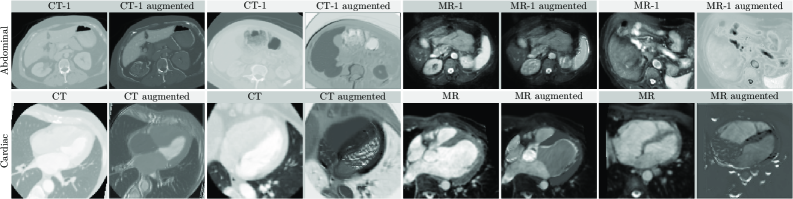

The average histogram of the source domain h𝒮¯h_{\bar{\mathcal{S}}} is only computed once during training and stored alongside the model for later use. Exemplary images before and after applying SM are shown in Figure 5. Our ablation study in Section 5.5 shows that SM achieves performance improvements that are complementary to SRC. Importantly, SM is very light-weight and efficient, imposing almost no computational overhead.

Refer to caption

Figure 5: Exemplary abdominal (row 1) and cardiac (row 2) images are shown before (cols: 1, 3, 5, 7) and after (cols: 2, 4, 6, 8) applying the proposed Source Matching (SM). Image contrast was adjusted for better visualization.